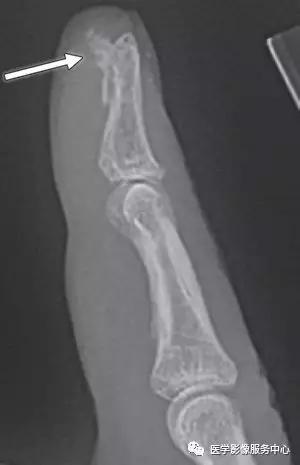

Mallet指:

(左)远端指骨背侧基底部末端伸肌腱插入处的小的撕脱骨片,伴轻微的远端指间关节屈曲。(右)软组织Mallet指,伸指总肌的终末肌腱的撕脱损伤,不合并撕脱骨折。